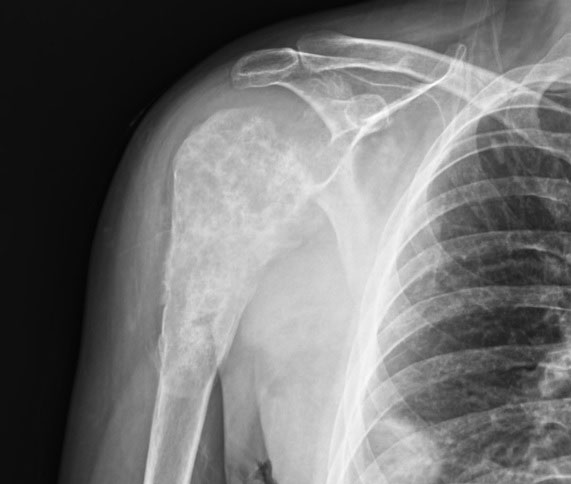

| Компьютерная томография (КТ) или магнитно-резонансная томография (МРТ) | Помогают получить детальные послойные изображения опухоли, оценить ее связь с окружающими тканями, состояние сосудов и второй почки. КТ грудной клетки обязательно проводится для исключения метастазов в легких. |